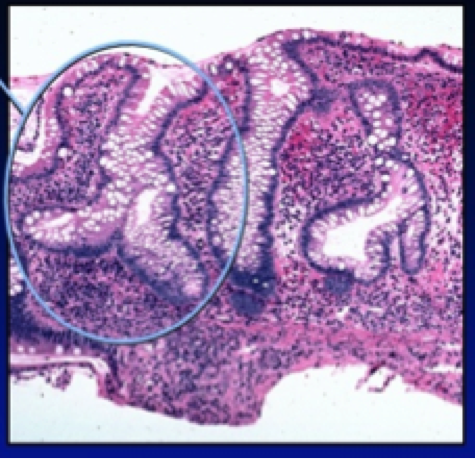

What is this? notable?

Crypt abscess in acute self-limited colitis

(probably infectious)

inflammatory infiltrate and crypt abscess formation are prominent as in ulcerative colitis, but the crypt architecture remains intact. The crypts are lined up straight, parallel, close to each other like a row of test tubes, and the bases reach the muscularis mucosa.